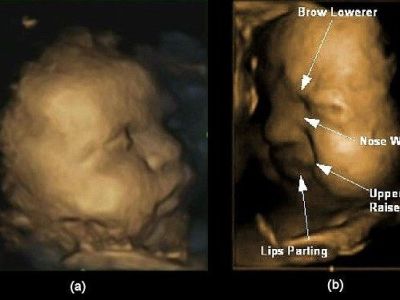

ΨΥΧΟΛΟΓΙΑ Tα αγέννητα μωρά εξασκούν τις εκφράσεις τους για τον τρόπο που θα αντιδρούν στον πραγματικό κόσμο! (φωτό)